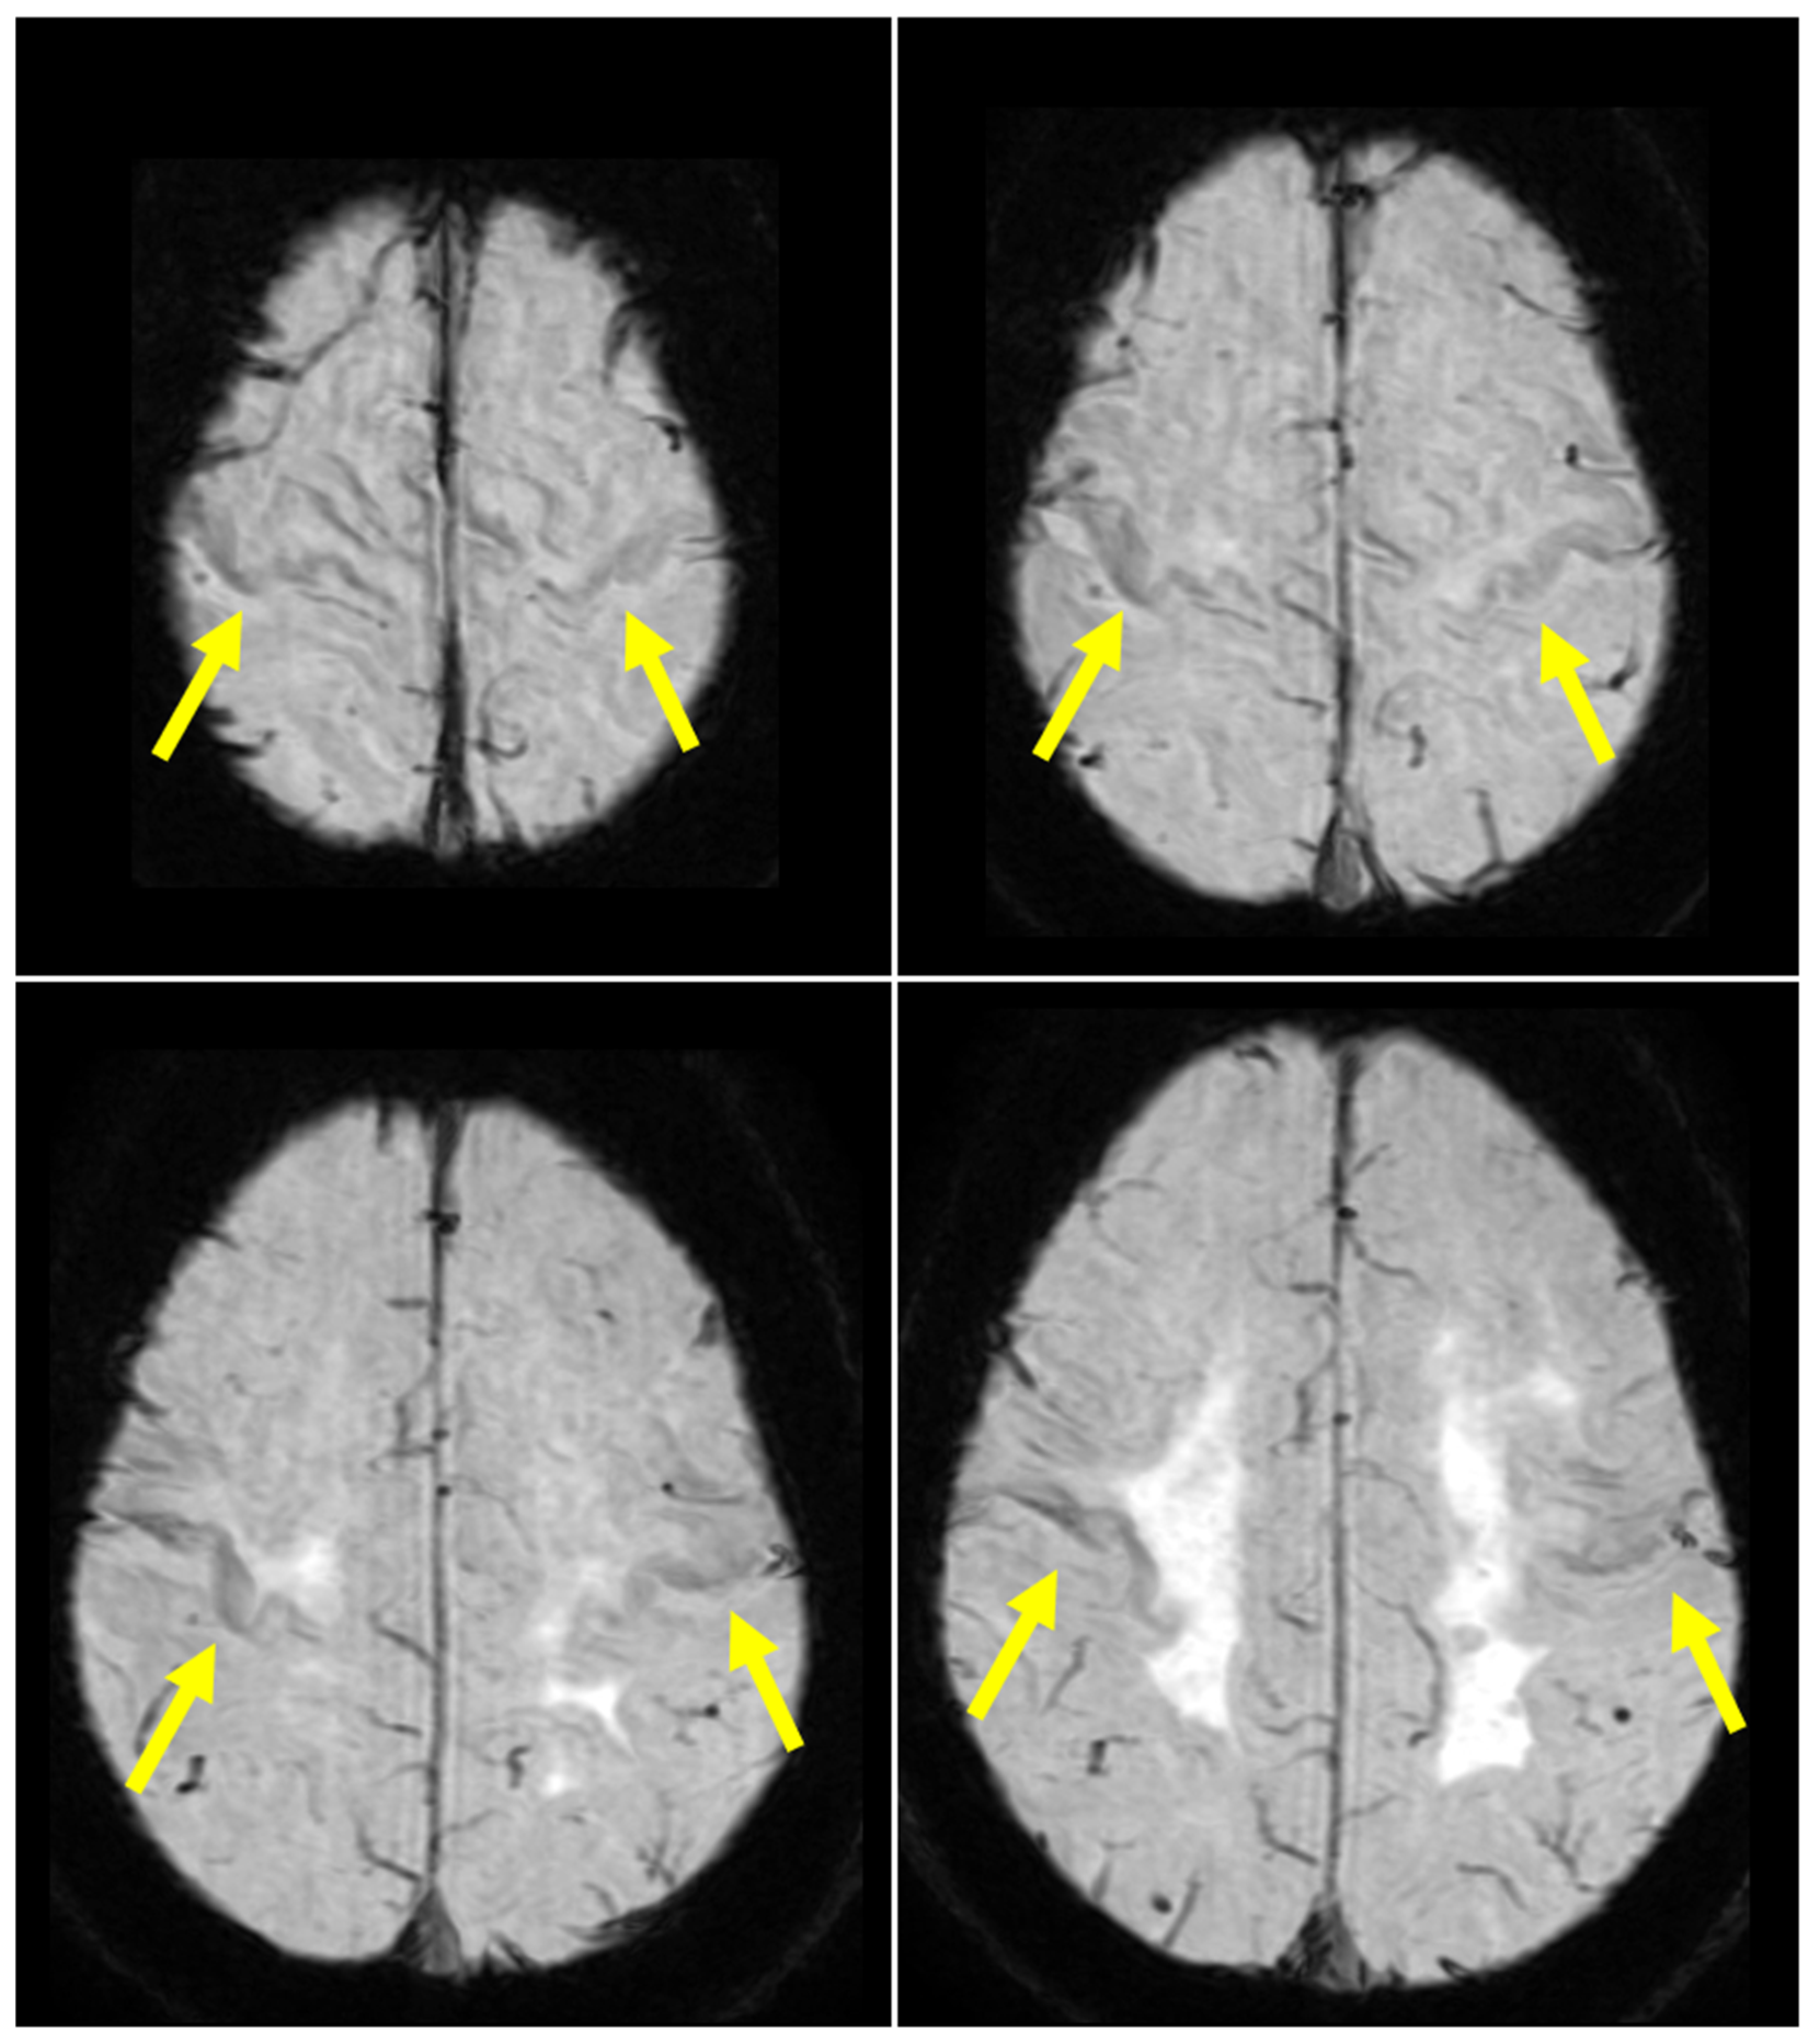

- Mohammadi, S.; Ghaderi, S. Motor band sign in motor neuron diseases using magnetic resonance imaging: A systematic review. Acta Neurol. Scand. 2023, 2023, e6677967. [Google Scholar] [CrossRef]

- Ghaderi, S.; Mohammadi, S. Motor band sign or biomarker. iRADIOLOGY 2023, 1, 378–380. [Google Scholar] [CrossRef]

- Chung, H.S.; Melkus, G.; Bourque, P.; Chakraborty, S. Motor Band Sign in Motor Neuron Disease: A Marker for Upper Motor Neuron Involvement. Can. J. Neurol. Sci. 2023, 50, 373–379. [Google Scholar] [CrossRef] [PubMed]